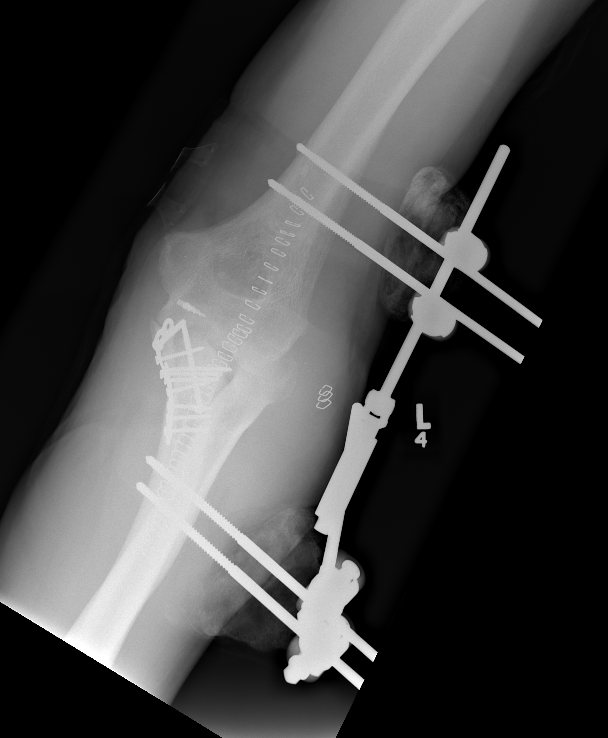

Fixed external fixation

AO surgery reference fixed external fixation

| Lateral humeral pin | Ulna pins |

|---|---|

|

Anterior to radial nerve

Subcutaneous border of ulna